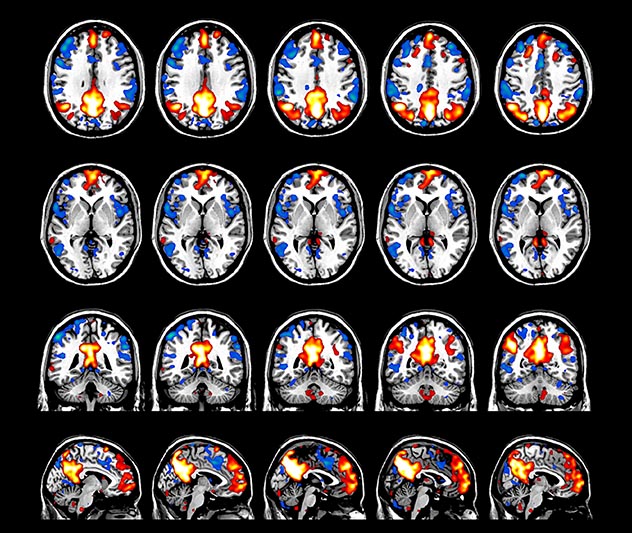

Imaging was performed using Ingenia 3T CX with a 32ch dS Head coil, TR 1.6 sec, TE 35 ms, voxel size 3.1 x 3.1 x 3.1 mm, 46 slices and Multiband SENSE factor 2. Image provided by Dr. Gispert

Default mode network as discovered by resting state fMRI in one participant of the ALFA cohort [7]. rs-fMRI allows us to find networks of brain regions with highly correlated activity and sustaining distinct brain functions. The default mode network (in warm color scale) is active when the brain is focused on introspective thinking and has been shown to be altered in Alzheimer’s. Interestingly, brain areas of this network are known to show abnormal levels of one of the pathological hallmarks of Alzheimer’s (b-amyloid deposition) in preclinical stages. We want to better understand the alterations of these brain networks in preclinical stages of Alzheimer's and explore their potential use as biomarkers.

Emotional n-back task combines a test of working memory with the use of emotive (faces) and neutral (places) images. The contrast in the images is between the activity when faces are presented compared to places, showing activation in the amygdala, fusiform, and occipital face areas.

Processing based on the Human Connectome Project (HCP) pipelines. The high resolution of the fMRI data allows extraction of the cortical surface, with minimal averaging of non-cortical signal. Surface based analysis provides improved cross-subject alignment, and prevents signal contamination between adjacent sulci.

Group analysis of 88 9- and 10-year olds part of ABCD, all scanned at UVM on Philips Achieva 3.0T dStream. Scale runs from red p=0.001 to yellow p<10ˆ-5. Images provided by Dr. Watts.

Acquisition using the ABCD protocol for fMRI with TR 800 ms, TE 30 ms, flip angle 52°, 2.4 mm isotropic imaging resolution with a 216×216×144 mm3 field of view using a MultiBand acceleration factor of 6 (60 slices, no gap). Two runs of 5 minutes per subject.